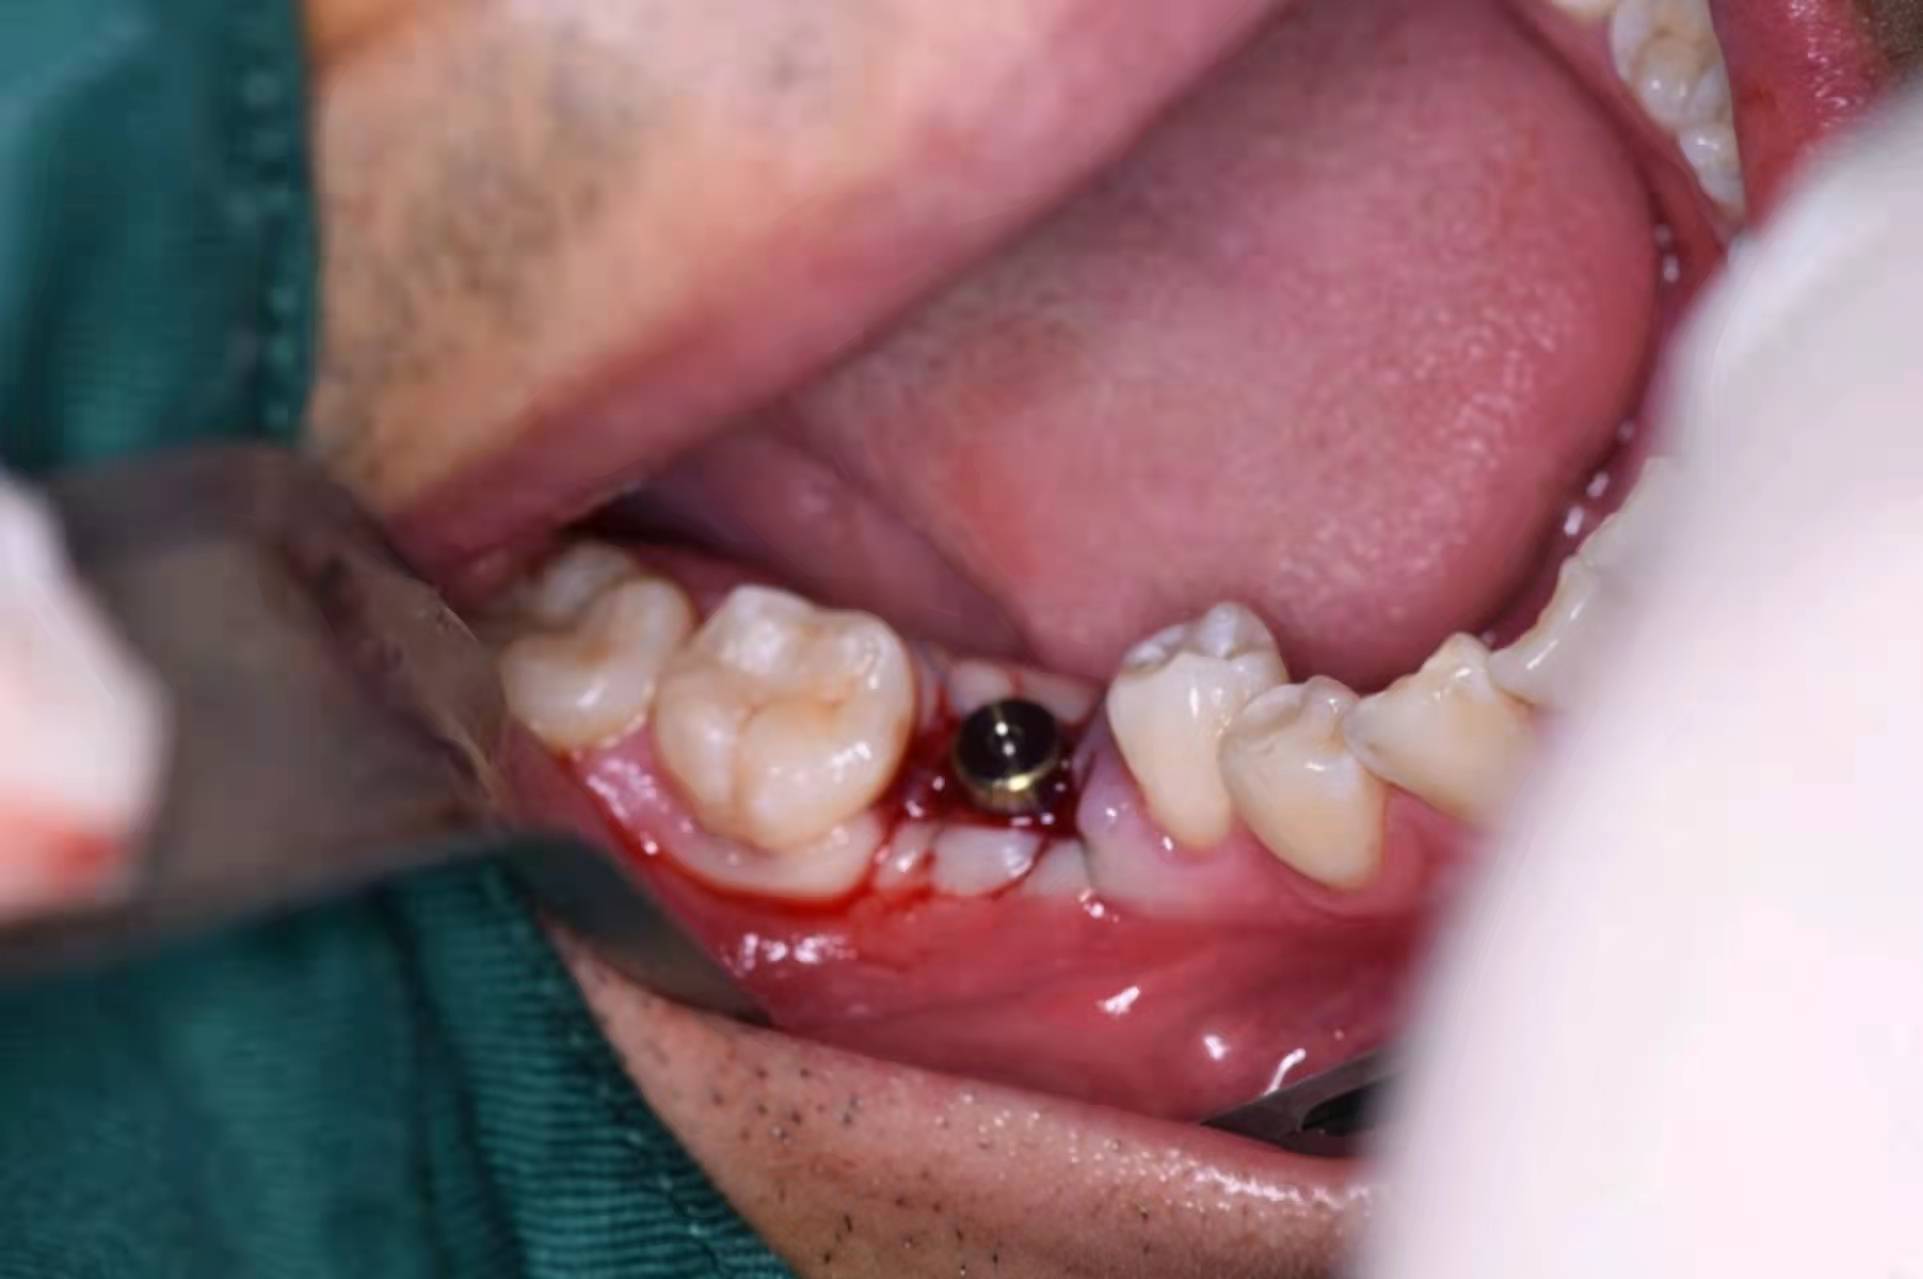

植入種植體(諾貝爾)

擰入愈合基臺: